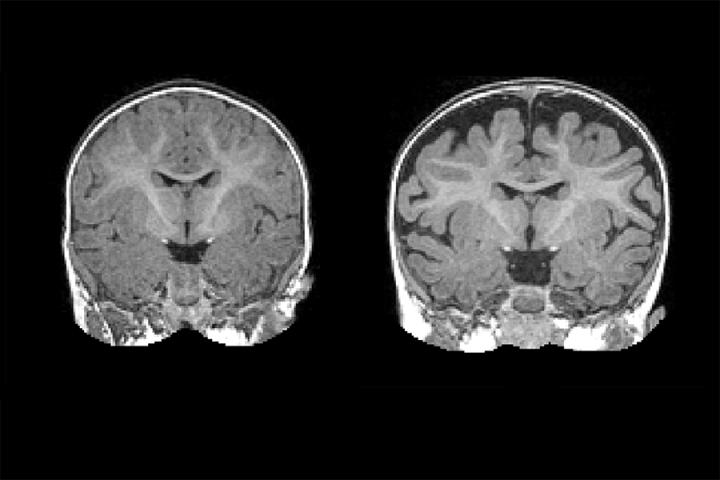

image: Right: MRI of a baby at 6 months who was diagnosed with autism at 2 years. The dark space between the brain folds and skull indicate increased amounts of cerebrospinal fluid. Left: MRI of a baby who was not diagnosed with autism at age 2. Note the decreased amount of CSF. view more

CHAPEL HILL, NC - A national research network led by UNC School of Medicine's Joseph Piven, MD, found that many toddlers diagnosed with autism at two years of age had a substantially greater amount of extra-axial cerebrospinal fluid (CSF) at six and 12 months of age, before diagnosis is possible. They also found that the more CSF at six months - as measured through MRIs - the more severe the autism symptoms were at two years of age.

The six-month olds who went on to develop autism had 18 percent more CSF than six-month olds who did not develop autism. The amount of CSF remained elevated at 12 and 24 months. Infants who developed the most severe autism symptoms had an even greater amount of CSF - 24 percent greater at six months.

The researchers found that increased CSF predicted with nearly 70 percent accuracy which babies would later be diagnosed with autism. It is not a perfect predictor of autism, but the CSF differences are observable on a standard MRI. "In the future, this sort of CSF imaging could be another tool to help pediatricians detect risks for autism as early as possible," Shen said.